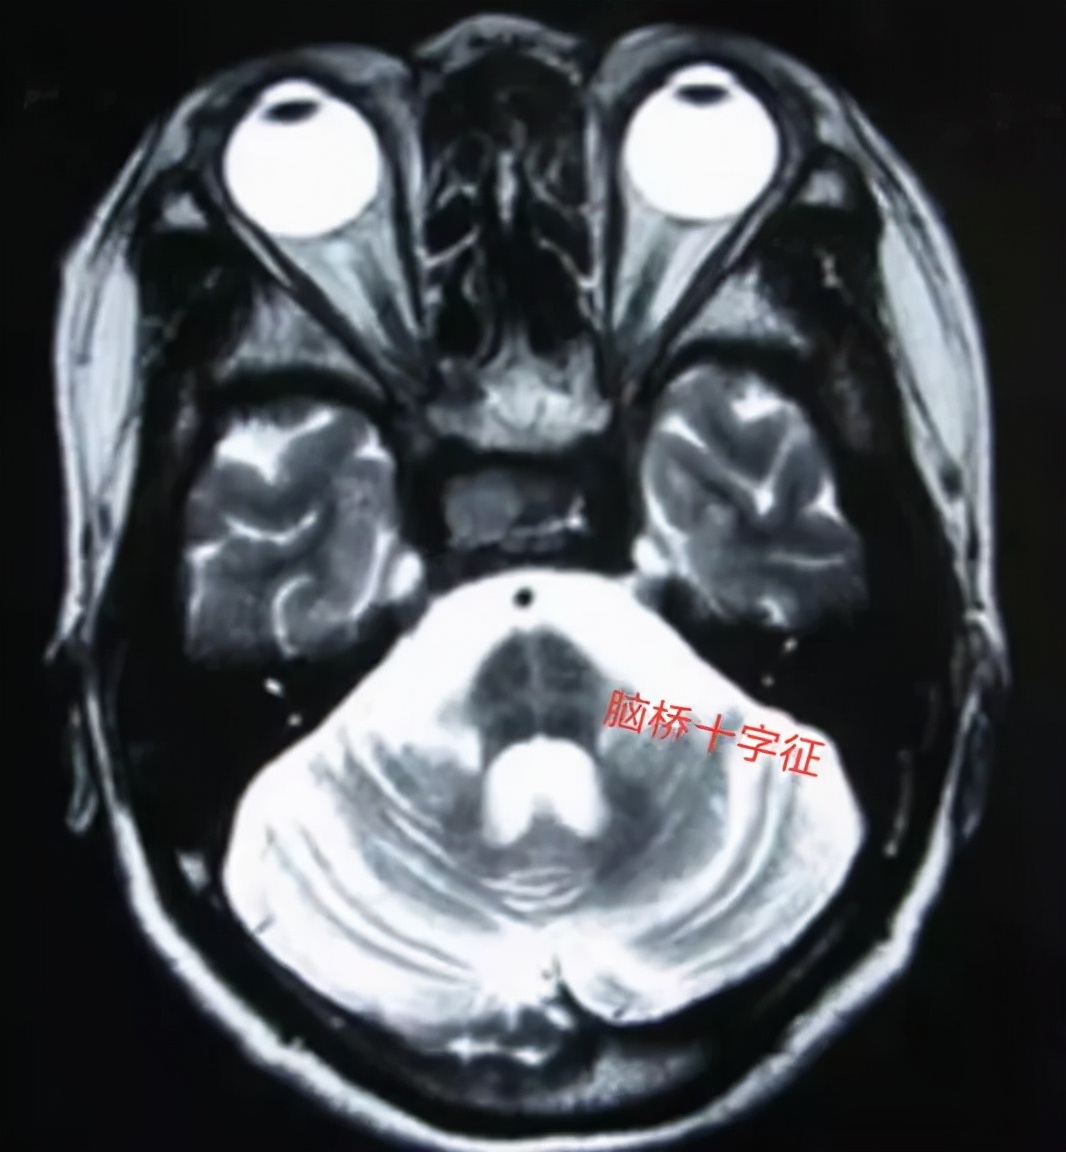

图 |核磁提示脑桥十字征